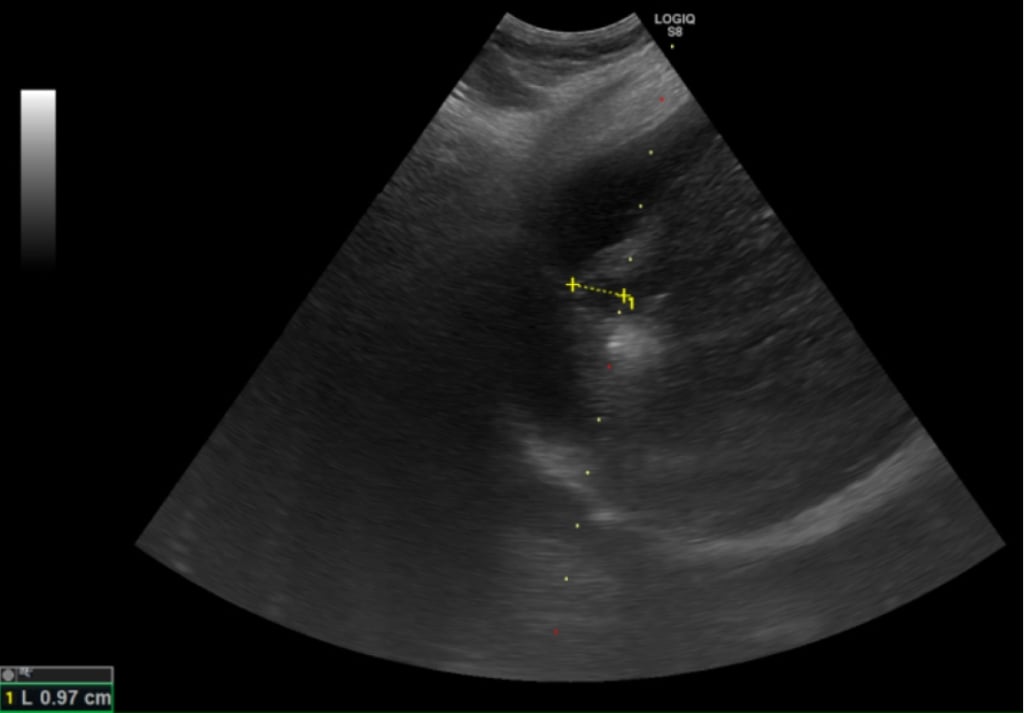

根據臨床數據,零期肝癌治療後平均存活率超過10年以上,若延誤至第二期則縮短為約5年,第三期降至2.5年,若已轉移,存活時間僅剩半年。「在第零期使用電燒治療普遍可根治,不需要化療,已經有遠處轉移才會考慮使用免疫療法及標靶治療。」鄭煜明醫師解釋,電燒治療是透過超音波導引定位,使用電極產生電流,造成離子震動產生超過60度的熱能氣化腫瘤,比起手術能更完整保留健康的肝臟組織。

醫師鄭煜明進一步說明,肝癌患者平均5年的復發率高達七成,因此電燒治療對於可能復發,需要多次治療的患者而言更具優勢,且此療法住院時間短,通常三日左右即可出院。適應症方面,電燒治療適用於單顆或三顆以下、每顆腫瘤不超過三公分的個案,且腫瘤位置不能靠近心臟、肺臟等重要器官。治療前需評估凝血功能,若有凝血嚴重異常且無法透過治療矯正者,則不適用電燒治療。